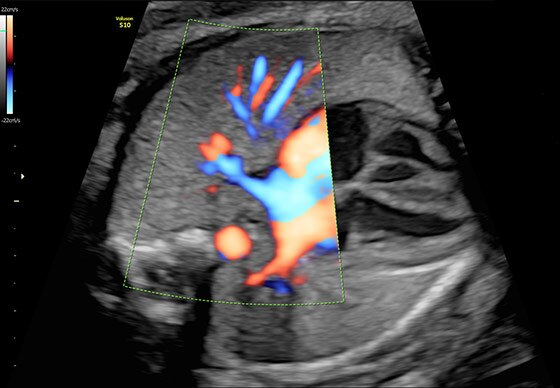

- Чувствительный цветовой доплер для оценки кровотока и анатомии сосудистого русла.

- Исключительная чувствительность при оценке анатомических структур и функций благодаря передовому цветовому допплеру